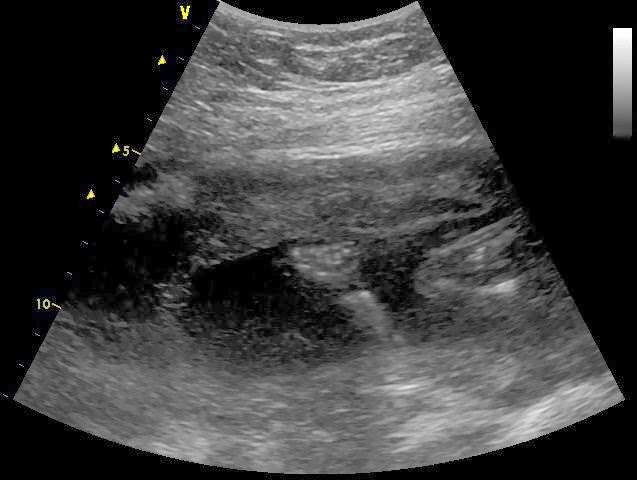

We all calling this baby “Shy Baby.” Twice now we have snuck (have snuck? sneaked? conjugate that for me.) in to have a quick ultrasound to look at the baby’s gender and both times, the baby has been very shy. Not shy like Lincoln, who just flat out refused to show his goods, this baby seems less ninja-like. I’m hardly feeling movement, and when I do it isn’t sharp or jabby, its slow and gentle. Shy baby. The last ultrasound we had we thought we had a really clear shot of the gender, then the baby moved and we had an entirely different shot which made us second guess. All my friends who are having babies around the same time as me know what they are having and I’m jealous.

| head and profile |

| a little hand with teeny fingers! |